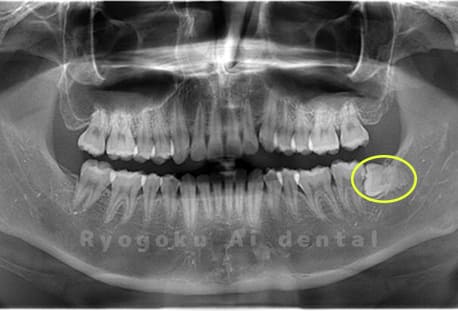

- 下顎左の水平埋伏智歯

-

- 治療内容

- 下顎左の水平埋伏智歯を抜歯したケースです。

<リスク・副作用>

手術後は痛み、腫れ、痺れなどの副作用が生じる場合があります。